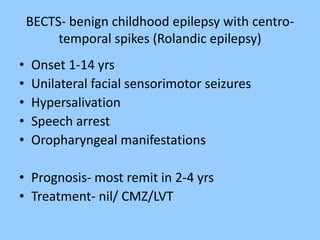

1. The document discusses EEG patterns and findings in various neurological conditions seen in children. It includes descriptions of normal EEG findings as well as abnormal patterns seen in conditions like absence seizures, West syndrome, benign childhood epilepsy with centrotemporal spikes, Lennox-Gastaut syndrome, non-convulsive status epilepticus, subacute sclerosing panencephalitis, and herpes encephalitis.

2. Case studies are presented with clinical histories and EEG findings to illustrate different pathologies. Treatment options are also mentioned for many of the conditions.